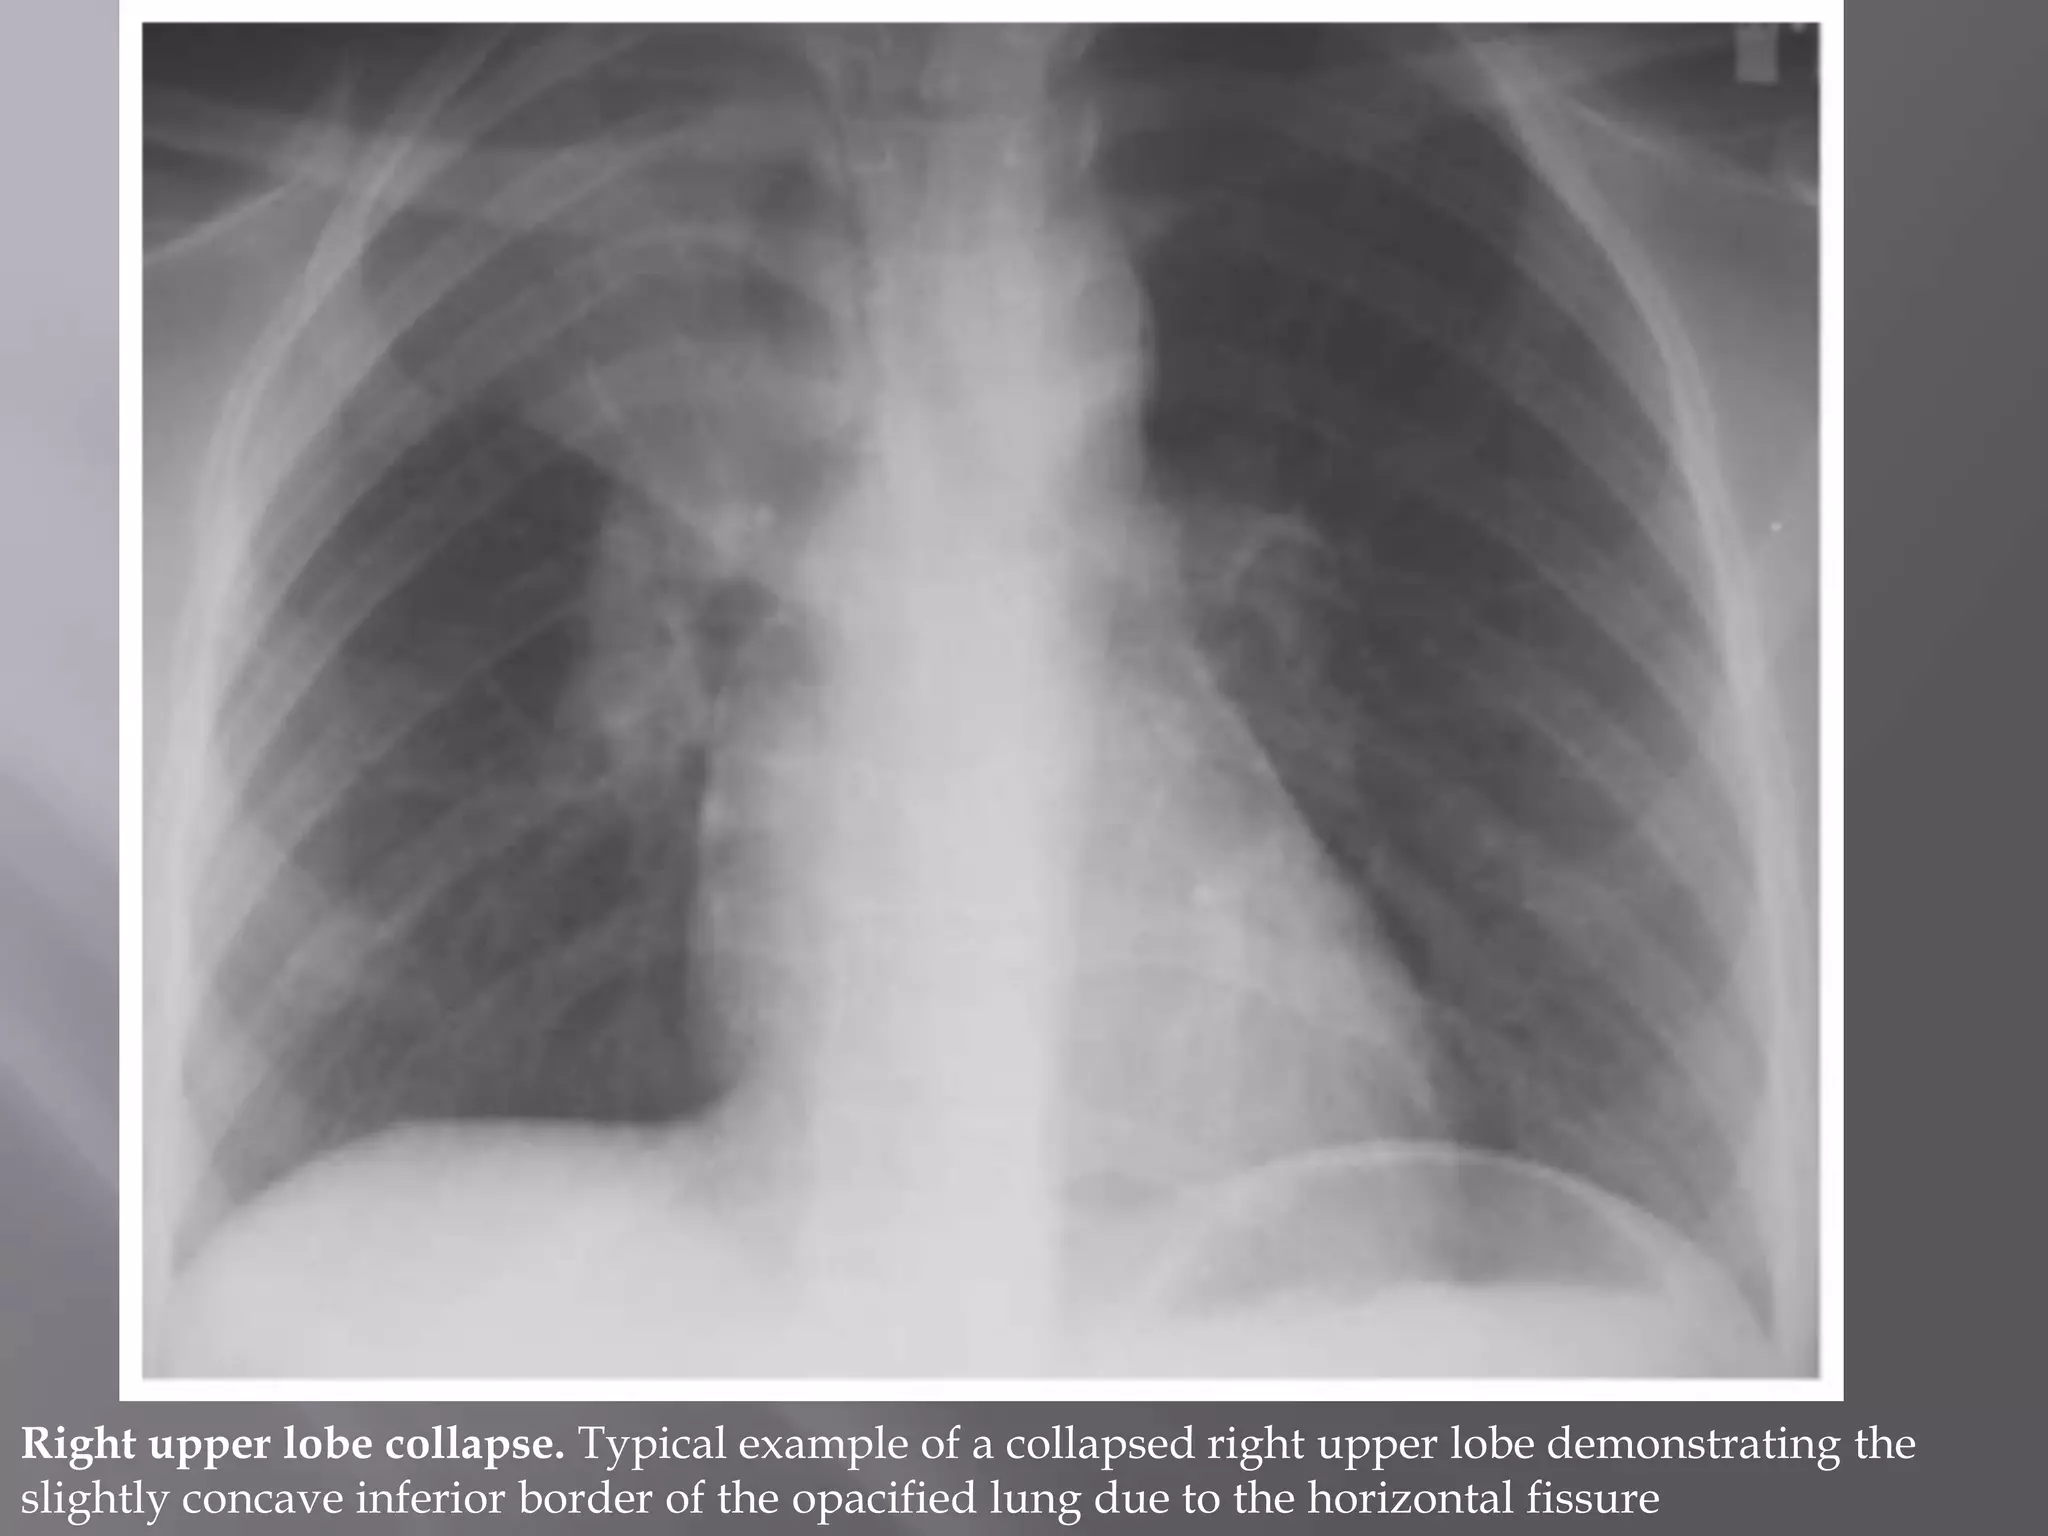

Right upper lobe collapse. Typical example of a collapsed right upper lobe demonstrating the

slightly concave inferior border of the opacified lung due to the horizontal fissure

Right upper lobecollapse. Typical example of a collapsed right upper lobe demonstrating the slightly concave inferior border of the opacified lung due to the horizontal fissure